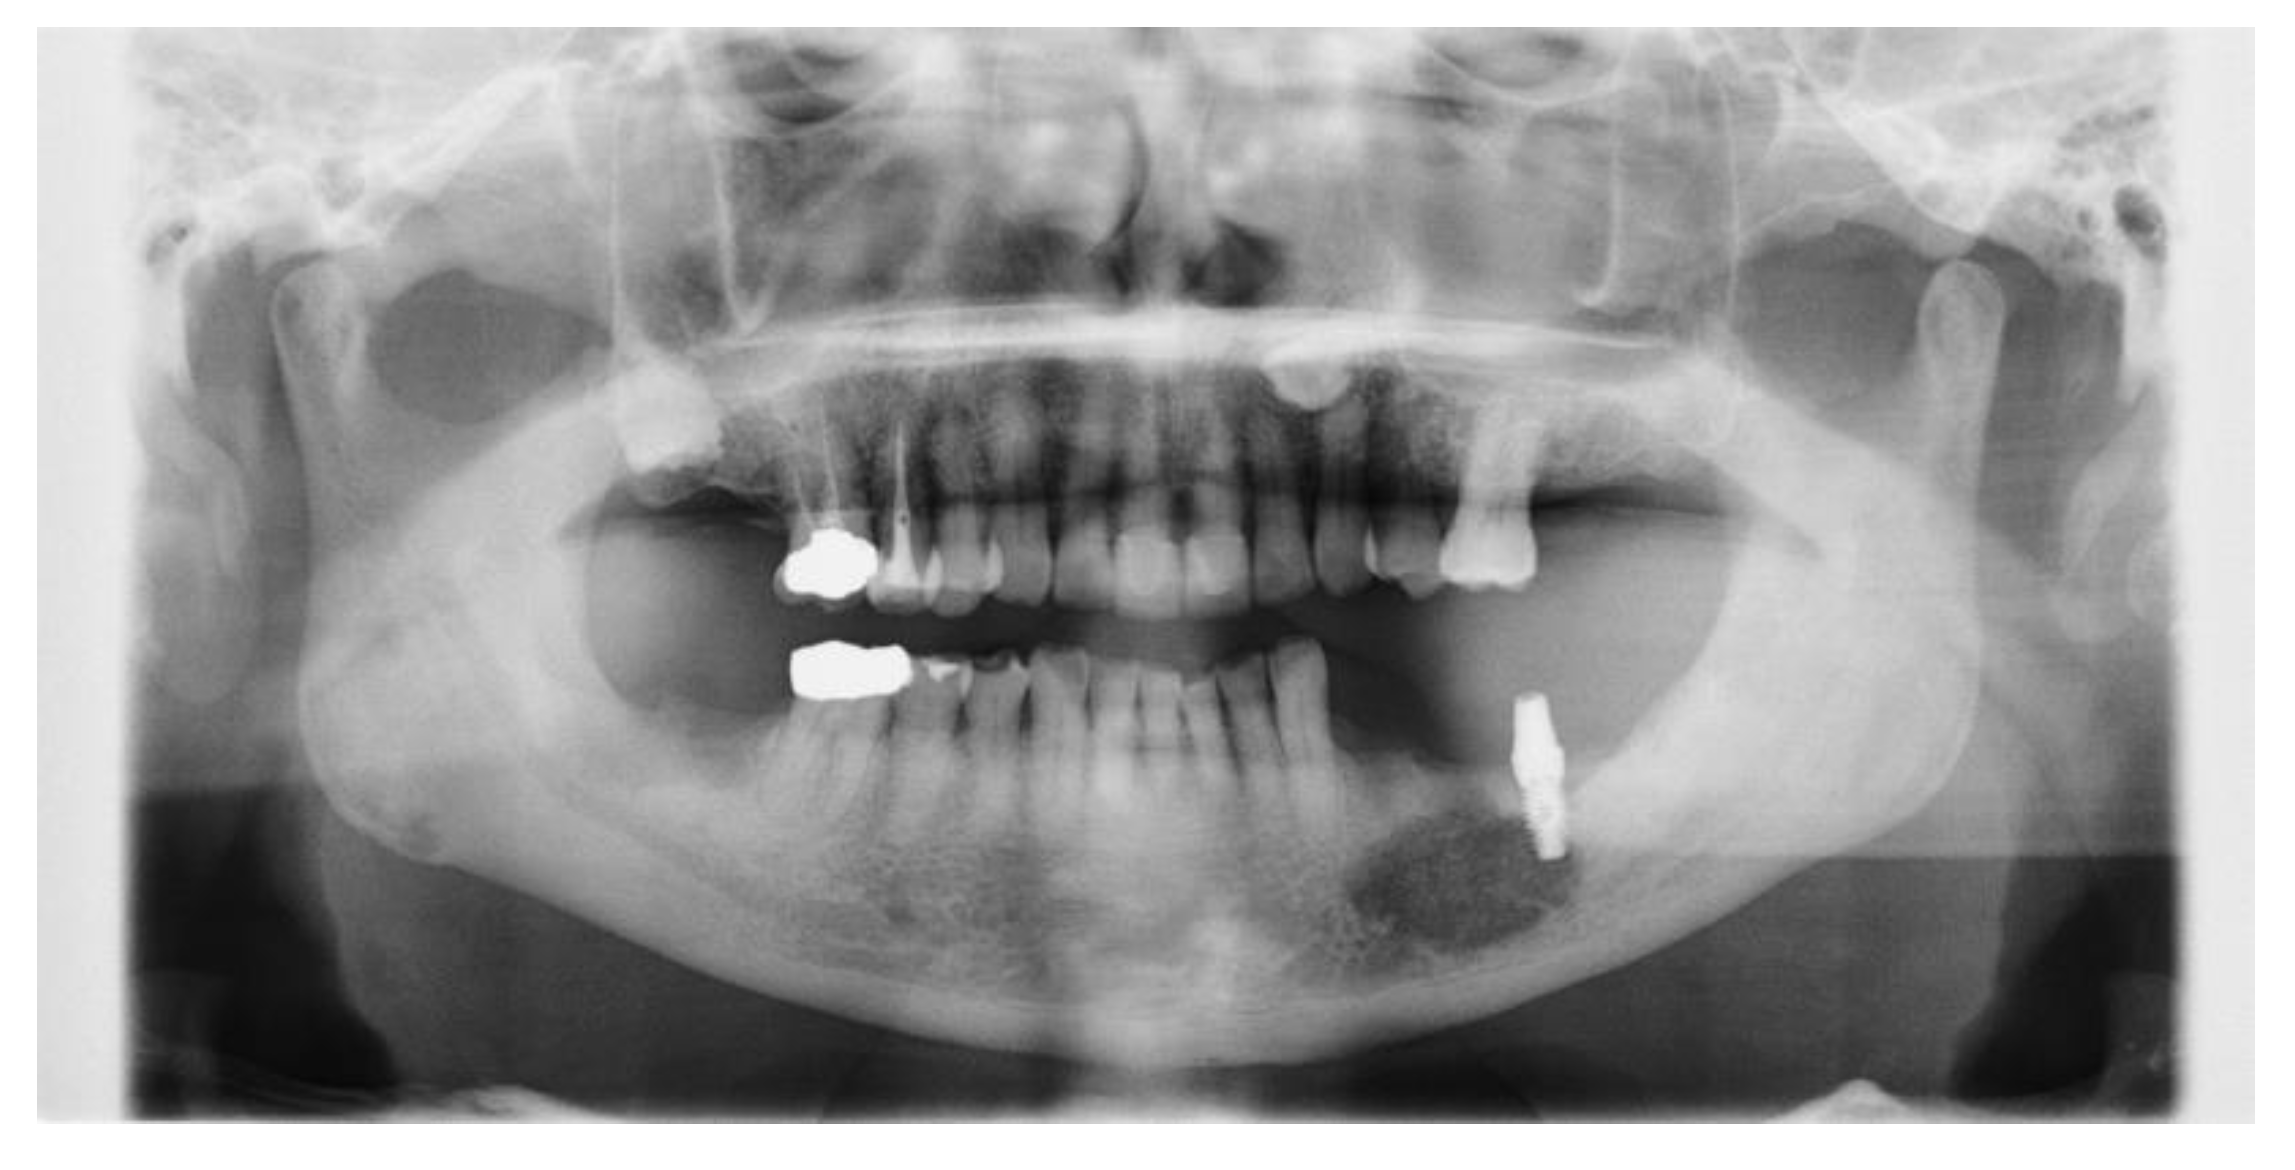

| 0 | First visit (Figure 1), | |||

| biopsy (Figure 2), | PV, peri-implantitis, S/O: gingival malignant tumor | SBCWPV (first) | ||

| start of steroid treatment | ||||

| 7 | (Figure 3) | Significant enlargement of the lesion due to bone melting at tooth 35 | ||